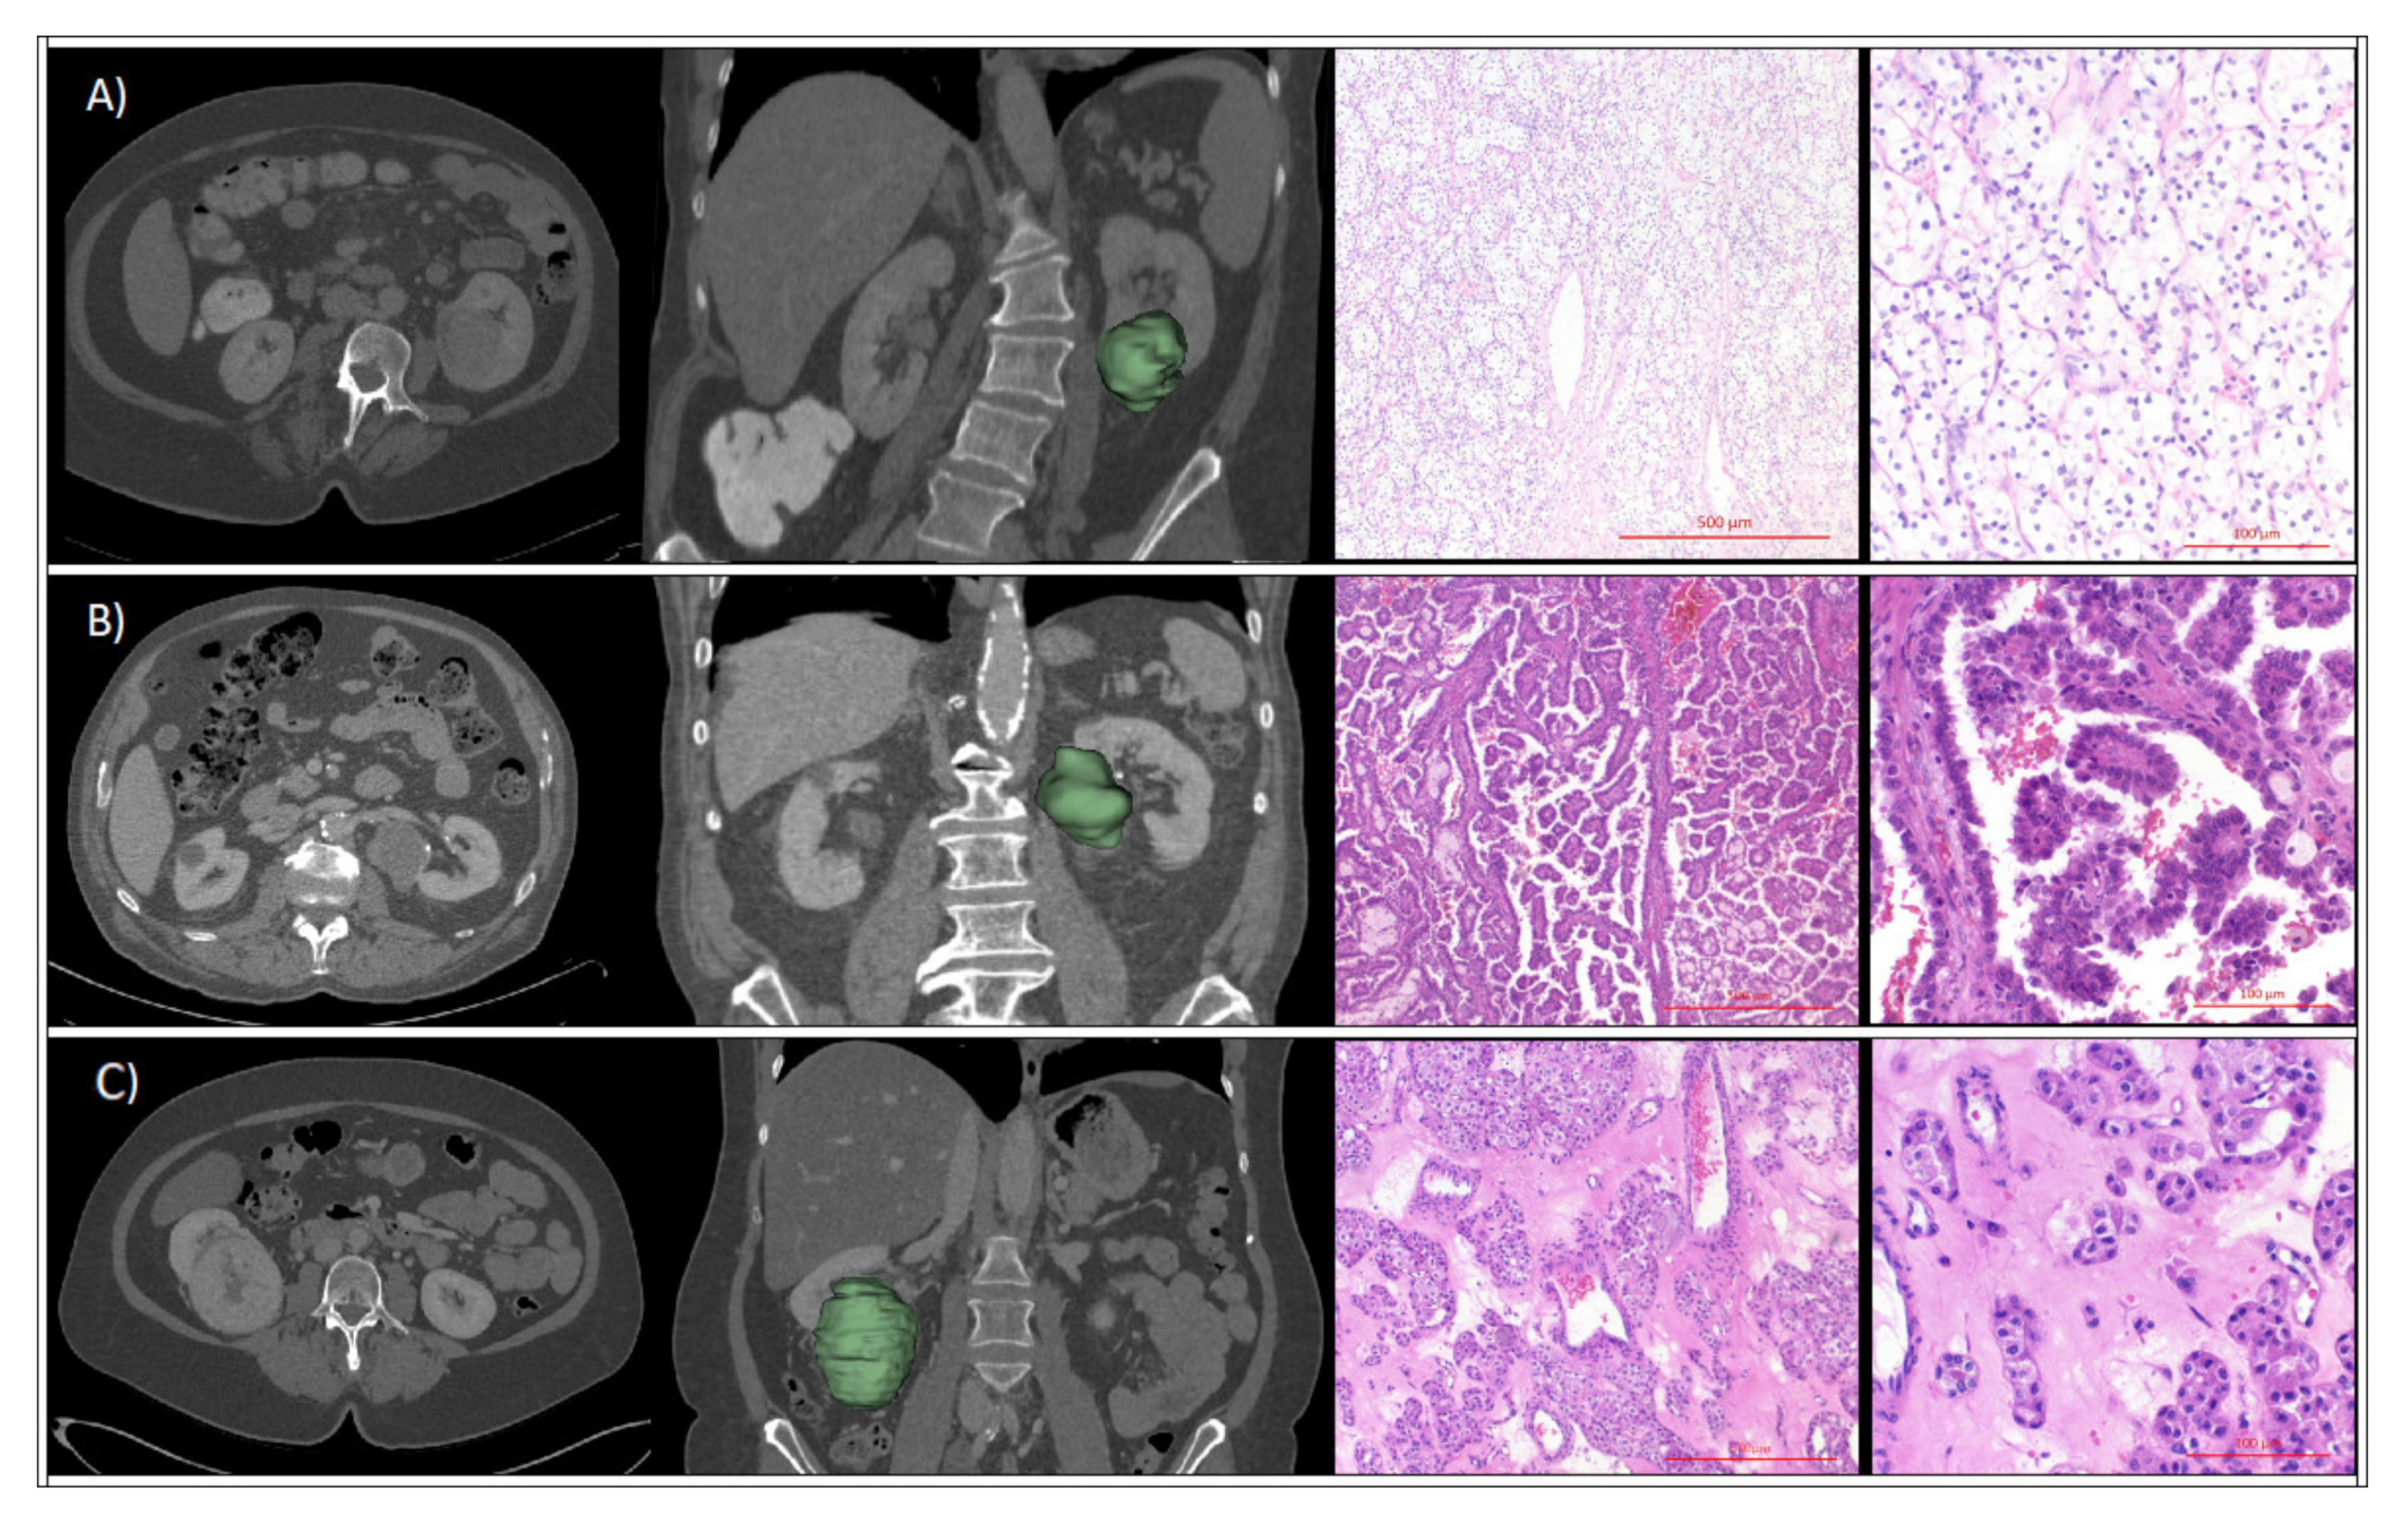

2. Results

4. Material and Methods

4.1. Study Cohort Selection

4.2. CT Imaging

4.4. Renal Tumor Assessment